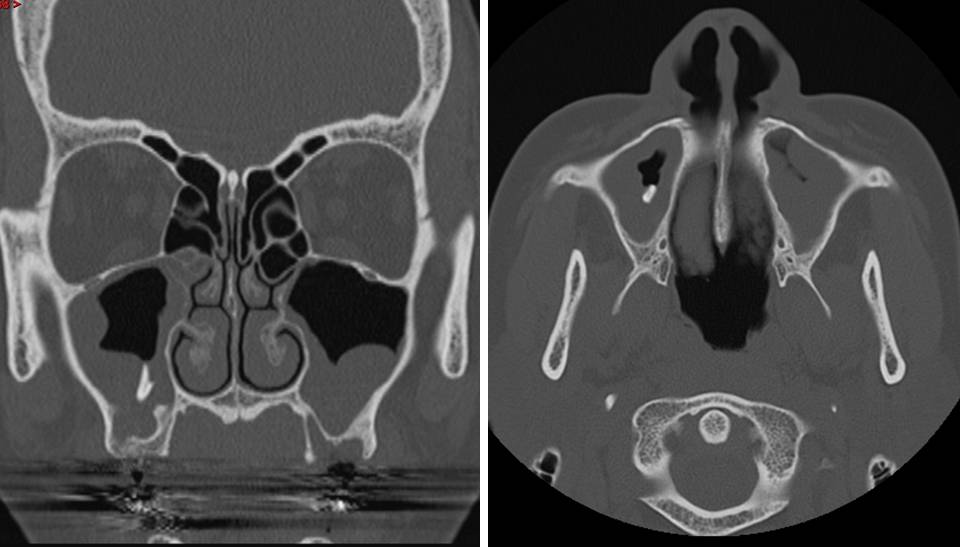

From www.globalradiologycme.com

Tooth Root in the Maxillary Sinus Tooth Extraction Air Sinus If you should, keep your mouth open to. this condition occurs when a dental infection caused by lack of oral hygiene or dental surgery, such as tooth. air pressure must not be increased in the nasal or sinus cavities. The first layer involves careful placement of collagen. signs of sinus infection after tooth extraction include red, swollen,. Tooth Extraction Air Sinus.